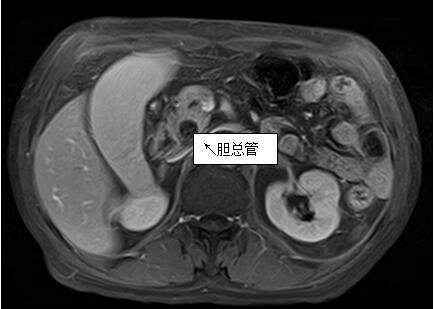

69歲王姓患者,因“發(fā)現(xiàn)無痛性黃疸1月”入院���,根據(jù)患者病史���,患者診斷傾向于壺腹部腫瘤所致梗阻性黃疸。予以完善腹部CT及上腹部MRI加MRCP均顯示肝內(nèi)外膽管擴張�,未發(fā)現(xiàn)明顯膽管,胰腺及十二指腸乳頭部腫瘤�����,且患者CA199正常����。以前醫(yī)院未引進超聲內(nèi)鏡��,這類患者到此就遇到診斷瓶頸�����。此患者經(jīng)過消化內(nèi)科張丹霞副主任醫(yī)師完善超聲內(nèi)鏡檢查后����,可以清楚顯示膽總管下段壁內(nèi)軟組織占位�����?����;颊咄ㄟ^超聲內(nèi)鏡檢查診斷明確�,轉(zhuǎn)至肝膽外科行手術(shù)治療。

上腹部MRI圖片